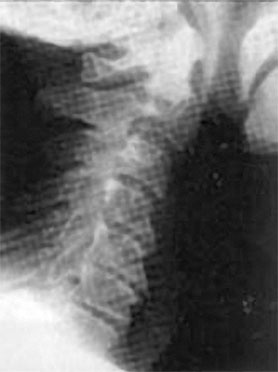

Вторит ему Говард Лэнгстайн (Howard Langstein), руководитель службы пластической и реконструктивной хирургии в университетской клинике: «Резорбция костной массы приводит к потере былой четкости овала и к провисанию мягких тканей. Внешне это проявляется в том, что нижняя часть лица приобретает более мягкие овальные очертания, снижается тонус кожи щек, подбородка и шеи, в результате чего очертания лица приобретают характерный возрастной вид». Далее Г. Лэнгстайн заявил: «Хотя врачи всегда знали, что кости со временем меняются, но как это проявляется с возрастом – не оценили». В свою очередь остеопороз черепа напрямую зависит от кровоснабжения головы. И мы опять приходим к неизбежности хорошего состояния «трубопроводов», несущих питание к мозгу и лицу. А перекрываться это питание может не только из-за сжатия артерий, но и всех сосудов шейного отдела, в том числе и вен. В этом случае артериальная кровь будет поступать, а отток будет заблокирован, что вызовет повышение внутричерепного давления и сильную головную боль. Головной мозг снабжается из двух сосудистых бассейнов. Первый составляют сонные артерии. Поражение этих артерий часто приводит к развитию острого нарушения мозгового кровообращения (инсультам). Ко второму относятся правая и левая позвоночные артерии. Их поражение не приводит к таким тяжелым осложнениям, как инсульт, но может способствовать головокружениям, усиливающимся при движениях головы или изменении положения тела. Подобные симптомы могут вызываться спазмами как позвонков, так и мышц шеи. К примеру, перенапряжение затылочных мышц зачастую ведет к головным болям и к проблемам со зрением. Так что шейный отдел позвоночника, состоящий из 7 позвонков, должен иметь и достаточную длину, и определенную статику (рис. 67). ![]() Рис. 67. Нормальная статика шеи. Правильный физиологический изгиб: А=А1 А что в действительности имеем мы? Обычно, даже при здоровом позвоночнике (только где его найдешь?), он начинает с возрастом деформироваться, «проседать», менять статику. Появляется симптом смещенной вперед и запрокинутой назад головы (рис. 68). ![]() Рис. 68. Гиперлордоз шейного отдела позвоночника: B > B1 В результате небольшой физиологический изгиб гипертрофируется, что ведет к проваливанию шейных позвонков вглубь шеи, особенно интенсивно при «сидячей» работе. Формируется гиперлордоз шейного отдела позвоночника. Чаще всего виной тому является не возраст, не тяжесть гравитации, а элементарно наша плохая осанка: сутулость, неправильная статика шеи, опущенная вниз голова, когда попытка смотреть в глаза собеседника достигается взглядом исподлобья за счет запрокидывания головы назад. Посмотришь на лицо, вроде бы женщина еще молодая, ухаживающая за собой. А взглянешь со стороны – прямо старушка ковыляет – ссутулилась, шейка вперед подалась, плечики сжались. Хорошо, сама себя не видит, а то бы очень огорчилась. Из-за того, что с возрастом диски между позвонками уплощаются, длина шеи укорачивается и частенько весьма значительно (рис. 69). ![]() Рис. 69. Шейный отдел позвоночника Появление поперечных морщин и складок на боковой поверхности шеи служит точной приметой этого явления. Проведите тесты – проверьте свою шею на ее статику – физиологический изгиб. Вот тут вам и пригодится второе зеркальце. 1. Возьмите его и внимательно рассмотрите свою шею в профиль и особенно сзади, приподняв волосы. Не стоит удивляться тому, что, возможно, там вы ее вообще не найдете – слишком коротким будет расстояние от первого позвонка до последнего – 7-го шейного, который легко прощупывается. В идеале длина шеи должна быть одинаковой по всей ее окружности. Если вам больше 40 лет, будьте готовы к тому, что, измерив свою шею, вы найдете сзади не более 2–3 см своей шеи. 2. Если запрокинуть голову назад, появляется ощущение, что в основание головы упирается кол – это ваш 7-й позвонок упирается в первый. Закономерно напрашивается вопрос: «А куда делись оставшиеся 5?» – запали внутрь шеи. И как бы ни было ухожено лицо, ни о какой молодости говорить уже не приходится. 3. Сравните длину вашей шеи с «эталонной». Похоже? Или…? Скорее всего или… Чтобы восстановить свою шею, недостаточно лишь массажами убрать жир с так называемой «холки» (кстати, основная часть этого горбика не жир, а отек лимфы) и «разбить остеохондрозные соли». В первую очередь необходимо восстановить статику шейного отдела. Ведь не «вытащив» запавшие вглубь шеи позвонки, характеризующие гиперлордоз шеи, вам никогда не приобрести четкого овала. При этом проблемы статики шейного отдела не ограничиваются возрастным гиперлордозом шейного отдела, когда шейные позвонки проваливаются вглубь шеи (рис. 70). Частенько, наоборот, этот изгиб может быть и излишне спрямлен (рис. 71). ![]() Рис. 70. Гиперлордоз шейного отдела ![]() Рис. 71. Спрямление шейного отдела позвоночника А вот для молодого поколения, особенно в наше время тотальной компьютеризации, характерен третий дефект неправильной статики шеи, который я назвала «компьютерной шеей» (рис. 72). Провоцируясь в большей степени именно вытягиванием шеи к экрану монитора, он выражается в ее вытянутости вперед и тоже сопровождается избыточным грудным кифозом – сутулой осанкой. ![]() Рис. 72. «Компьютерная» посадка шеи При такой статике центр тяжести головы (ЦТ) смещен вперед относительно центра тяжести тела (рис. 73). |